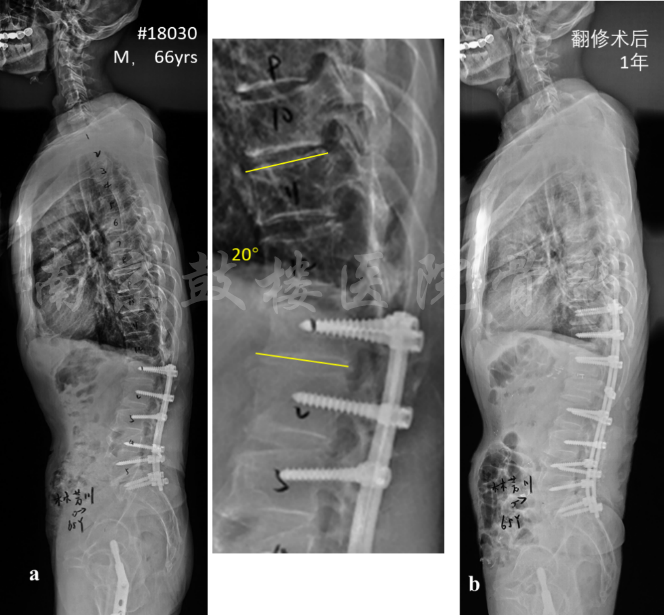

成人脊柱畸形术后近端内固定失败主要包括:(1)近端交界性后凸或近端交界性失败(PJK/PJF)(图1);(2)近端整体后凸合并矢状面失平衡。影响PJK发生的手术因素包括内固定的类型、手术方式、近端弯棒曲率、融合节段选择等。同时,手术时对于上固定椎的暴露过度以及过多破坏后方韧带复合体也会增加PJK发生率。

图1 男,66岁,半年前因腰椎管狭窄于当地医院行L1-S1内固定减压融合术,术后2年出现近端交界性后凸,PJA角度20°,伴T12-L1椎管狭窄;于我院行翻修术,去除松动的L1螺钉,行T12-L1 TLIF并将内固定上延至T10,术后1年无PJK(b)